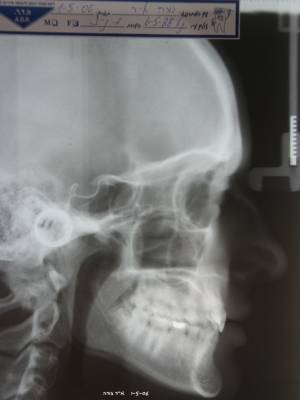

Je me suis permis de rectifier la Rx. pour avoir une idée du profil

@+ Bjc.

D’un point de vue orthodontique, , je ne vois personnellement que la zone incisivo-canine inférieure à traiter pour rajouter une incisive et je ne toucherais pas au reste.. Le fait qu’il y ait alors que trois incisives n’a pas d’importance ( il n’y a de toute façon pas la place d’en rajouter deux).

Compte tenu du manque d’os au milieu mandibulaire, je serais tenté d’y déplacer 32 pour en amener.

aux vues de la pano et de la photo intrabuccale,je ne pense pas qu'il y ait assez de place pour un implant (vous confirmez les implantos?),il faudra certainement ouvrir en reculant un peu les 4 et fermant les espaces anterieurs

d'un point de vue esthétique il est préférable de distaler les canines et de mésialer les incisives inf....pour les canines...c'est une question de forme...pour les incisives...il est plus facile de gérer la gencive périimplantaire si 1 implant est encadré de 2 dents naturelles qu'entre 2 implants